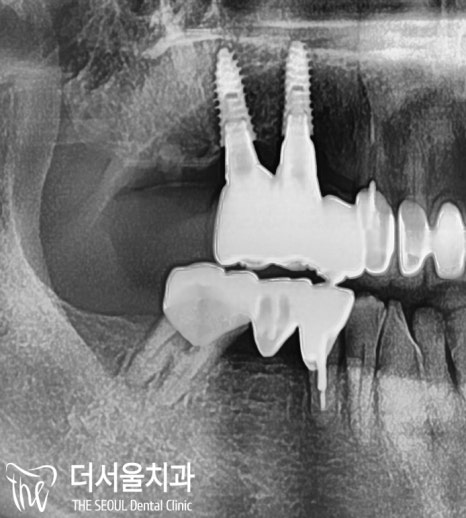

【 픽스처 식립 완료 】

계획된 위치와 각도에 맞춰

픽스처를 식립해줍니다.

이제 잇몸뼈(치조골)와 잘 붙기를 기다립니다.

뼈이식까지 함께 진행했기 때문에

회복 기간은 4개월이 걸렸는데요.